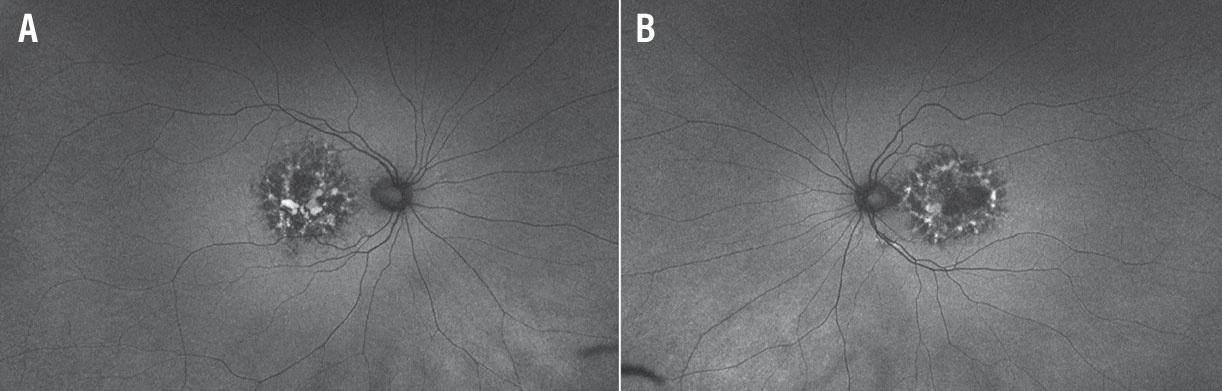

A fundus examination of the right eye (Figure 1A) revealed parafoveal pigment clumps with scattered yellowish fleck-like deposits interspersed with areas of retinal pigment epithelial atrophy. The fundus evaluation of the left eye (Figure 1B) demonstrated similar though less extensive findings with a prominent area of RPE atrophy in the temporal macula. The peripheral retina was unremarkable in both eyes.

Figure 1. Wide-field pseudocolor fundus imaging of the right (A) and left eyes (B) demonstrate parafoveal pigment clumping interspersed with yellow subretinal deposits and areas of retinal pigment epithelial atrophy. |